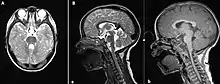

The disorder is characterized by absence or underdevelopment of the cerebellar vermis and a malformed brain stem (molar tooth sign), both of which can be visualized on a transverse view of head MRI scan.[16] Together with this sign, the diagnosis is based on the physical symptoms and genetic testing for mutations. If the gene mutations have been identified in a family member, prenatal or carrier diagnosis can be pursued.[4]